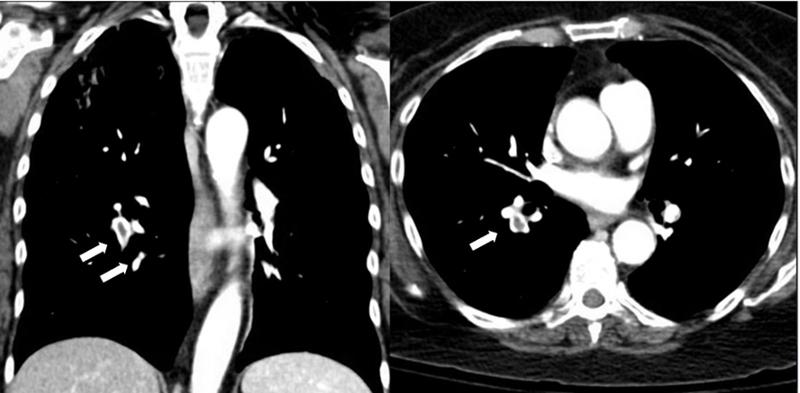

A 57-year-old female with a history of rheumatoid arthritis on chronic prednisone and methotrexate was admitted to the hospital with acute hypoxic respiratory failure. She was initially admitted to the medical intensive care unit (ICU) with a diagnosis of pneumonia but she did not improve with antibiotics. Given her risk factors for opportunistic infections, a diagnostic bronchoscopy with linear endobronchial ultrasound (EBUS) was performed. An abnormality in the pulmonary artery was noted (Figure 1).

Figure 1